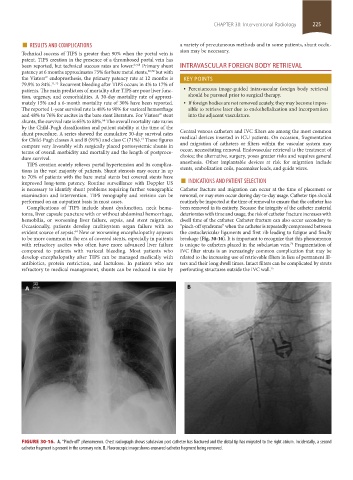

FIGURE 30-16. A. “Pinch-off” phenomenon. Chest radiograph shows subclavian port catheter has fractured and the distal tip has migrated to the right atrium. Incidentally, a second

catheter fragment is present in the coronary vein. B. Fluoroscopic image shows ensnared catheter fragment being removed.